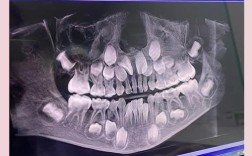

全景片:

- 显示全口牙齿(包括未萌出的恒牙胚)的发育、位置、形态、数量。

- 观察牙根情况(弯曲、吸收)、牙槽骨状况。

- 评估颌骨内是否有阻生牙、多生牙、囊肿、肿瘤等异常。

- 显示乳牙滞留、早失情况。